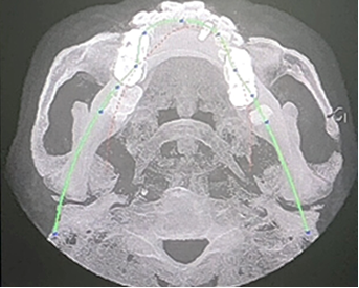

术前CBCT

21颊侧牙槽骨吸收至根尖,腭侧牙槽骨吸收至根尖1/3,根周可见低密度影。牙槽嵴宽度6.41mm。

局部反合、患牙长期牙周病变,骨质缺损,但软组织无明显缺失,为II类拔牙窝形态。

22冠状位CBCT情况

唇舌牙槽嵴宽度6.41mm,垂直骨缺失1/2,软组织无垂直向缺失。

术后即刻CBCT

术后CBCT

术前术后CBCT对比

唇侧过量植骨希望最终能够实现存量骨组织>2mm。

术后即刻与术后4.5个月CBCT对比

可见种植体唇侧顶端有一定骨粉吸收,但仍在预期范围内。